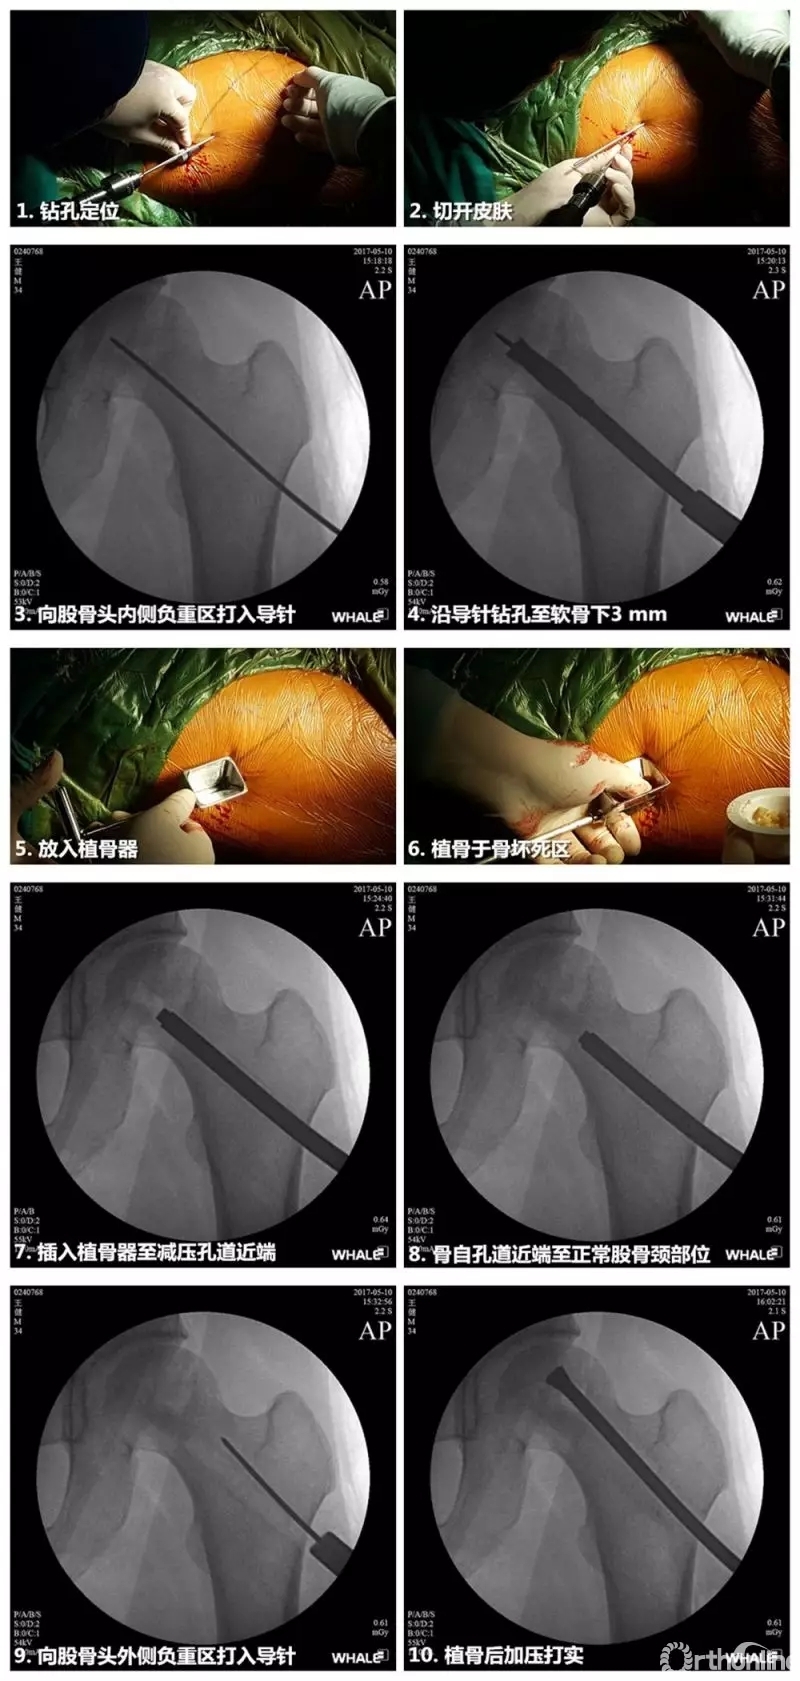

总结自己20年的临床经验,郭晓忠主任毫无保留地向大家详细讲解了“微创的经大粗隆单一入路双孔道减压植骨+结构性骨支撑手术”的手术方法。该手术的主要步骤包括:手术经大粗隆单一入路,沿股骨颈减压至股骨头内侧负重区,植入异体松质骨,并加压打实。沿股骨颈外侧减压至股骨头外侧负重区,植入异体松质骨,并加压打实。测量外侧减压孔道长度,植入羟基磷灰石聚酯棒结构性骨支撑棒。